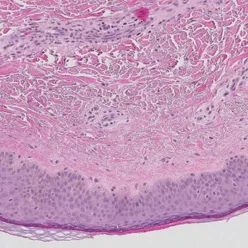

Patologiens morfologiske (struktur), immunhistokjemiske (proteiner) og molekylære analyser (arvestoff) er helt sentralt i arbeidet med kreftdiagnoser. Vi ønsker å forbedre patologidiagnostikken gjennom å finne, validere og ta i bruk nye biomarkører. Vi skal nå dette målet ved å ta i bruk storskala-analyser for proteiner og arvestoff, kunstig intelligens og digital patologi.

- "Who are at risk of developing cervical cancer?" Utvikling av nye biomarkører som kan forutsi hvilke kvinner som har risiko for å utvikle livmorhalskreft. Fokus på immunforsvar og genetiske endringer i vevet. Samarbeidsprosjekt med Kreftregisteret og Sørlandet sykehus.